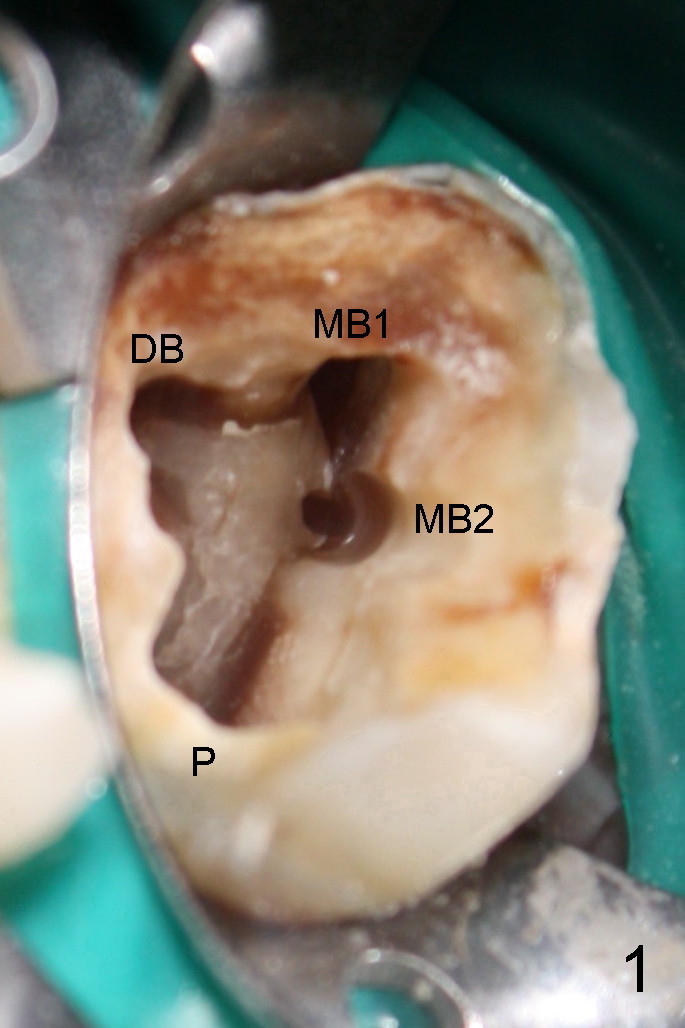

今天给一位二十四岁黑人做根管治疗:左上五(完成:三个根管)和七(开始)(图三),由于他的牙齿大,龋齿也大,根管口特别好找,包括MB2(图一),MB1,DB,P 扩大至二十号hand file;MB2扩大至20/.06 rotary file(还使用#2 Gates-Glidden file扩大MB2根管口)。由于时间不够,病人累了,paper point吸干根管后,拍摄图一(mirror view)。

第一:MB2在MB1舌侧1-3毫米,如果在MB1和P之间画一条线(图二红线),MB2又在红线近中0.5毫米,淡蓝色线与红线垂直。

第三:对所有上颌磨牙应该常规寻找MB2,花不了太多时间,也不难,也就是在MB1和P之间黑线(map),用超声波Piezo tip往根尖方向去除牙本质1-4毫米。如果黑线消失,说明是侧枝根管,不必继续探索。